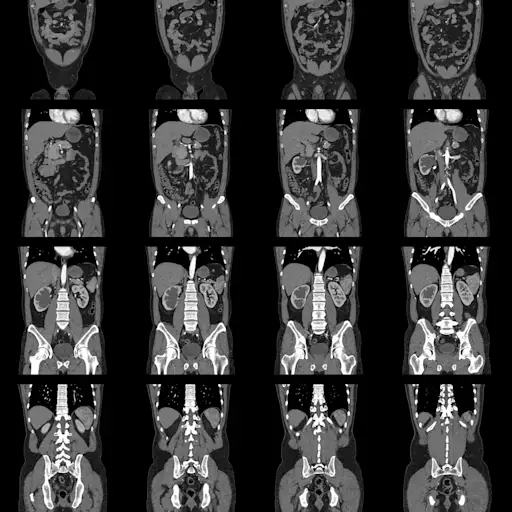

注意无症状结肠癌

结肠癌并不总是通过BMs发出警告信号。“早期结肠癌可能完全没有症状,可能在结肠镜检查、腹部CAT扫描或其他影像学检查中偶然发现。或者在标准血液测试中发现,”波普尔博士说,或者通过专门寻找一种由结肠癌产生的名为癌胚抗原(CEA)的化学物质的测试。这就是为什么在45岁的时候开始结肠镜检查很重要,如果你有家族史或炎症性肠病史,那么就应该尽早开始。